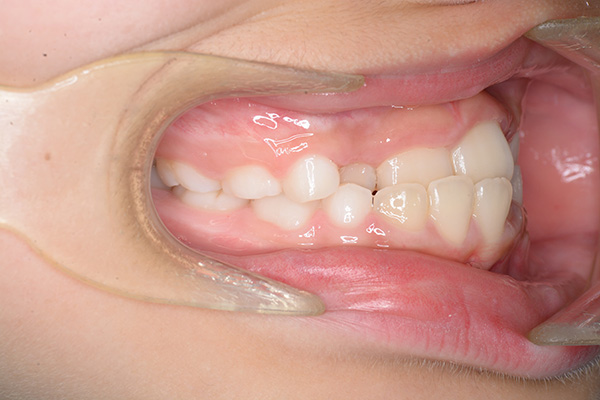

経過観察(13歳10ヵ月)

経過観察

(13歳10ヵ月)

批評・予后 上顎前歯のアライメントを行ったことで、ロッキングされていた上顎歯槽基底骨の成長に良い影響が生じており、側方歯群の交換も順調に進んでいる症例である。2期治療は相談の上、希望があれば行うこととしている。